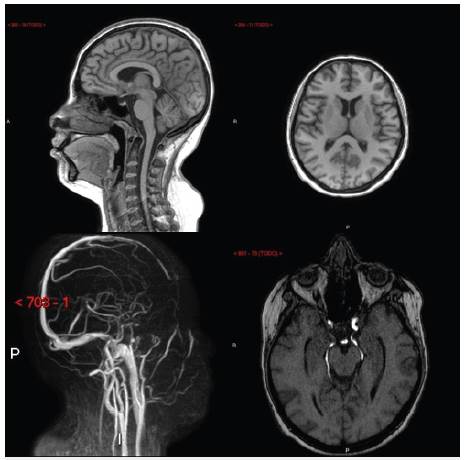

Una mujer de 19 años consultó a un hospital de alta complejidad del sur de Colombia por 10 días de evolución de cefalea holocraneana, sorda, no irradiada, que no empeoraba con las maniobras de valsalva, asociada a nausea sin emesis, sin foto o fonofobia y que no cedía a analgésicos. Concomitantemente tos, en ocasiones productiva asociada a disnea de grandes esfuerzos y fiebre subjetiva. Negaba otra sintomatologia adicional. La paciente tenía antecedente de LES diagnosticado dos años antes durante un episodio de trombosis venosa profunda de miembro inferior, momento en el cual adicionalmente se le realizó diagnóstico de síndrome de anticuerpos antifosfolípido (SAF) con anticoagulante lúpico y antibeta2 glicoproteina positivos al ingreso así como 12 semanas después. Así mismo, tenía diagnóstico histopatológico de nefritis lúpica clase IV (glomerulonefritis proliferativa difusa, clasificación de la Sociedad Internacional de Nefrologia / Sociedad de Patología Renal). Estaba en manejo con prednisolona 10 mg día y a pesar de habérsele indicado micofenolato mofetilo no lo estaba recibiendo por limitaciones de acceso a su entidad prestadora de servicios de salud. Al ingreso tenía presión arterial 110/70 mmHg pero taquicárdica (115 por minuto), taquipneica (22 por minuto) y desaturada (88% aire ambiente) con un índice de masa corporal de 26 kg/m2. El examen neurológico era normal, incluyendo la fundoscopia. Se identificaron estertores bilaterales e hipoventilación basal izquierda sin otros hallazgos de relevancia. Los paraclínicos se muestran en la tabla 1. La radiografía de tórax puso de manifiesto un derrame pleural izquierdo, que dado condición de inmunosupresión se decidió evaluar con tomografía de tórax, documentándose en esta una consolidación alveolar ipsilateral (no evidenciada en la radiografía). Ante sospecha de cuadro neumónico, favorecido por estado de inmunosupresión, se inició cubrimiento antibiótico empírico con ampicilina sulbactam a dosis de 3 gramos cada 6 horas. Se realizó punción lumbar que mostró aumento de la presión de apertura, 80 cms H2O (normal 5 - 20 cms H2O) con estudio infeccioso negativo y citoquímico normal (Tabla 1). La panangiografía cerebral (realizada para descartar trombosis de senos venosos dado antecedente de SAF), resonancia magnética cerebral simple y contrastada y la angiorresonancia cerebral (Figura 1) no identificaron lesiones o defectos vasculares.